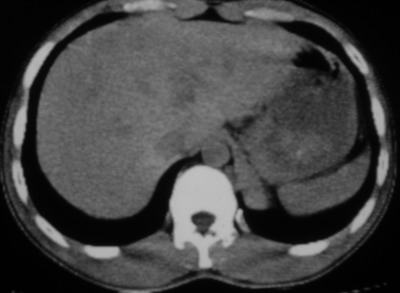

以下是引用余辉在2007-6-16 20:47:00的发言:[br]图像不边续,1左肺下叶膈后囊性病灶,与胃有密切联系,考虑局限性膈膨隆,不排除其他如脓肿等;2左膈肌脚增厚,其前方肝胃间隙内可见球形病灶,左肾上腺病变?进一步检查

以下是引用xulianj在2007-6-16 21:14:00的发言:[br]左膈肌脚增厚,支持膈肌角病变。

以下是引用卜一在2007-6-17 4:50:00的发言:[br]左膈肌脚增厚,支持膈肌角病变。